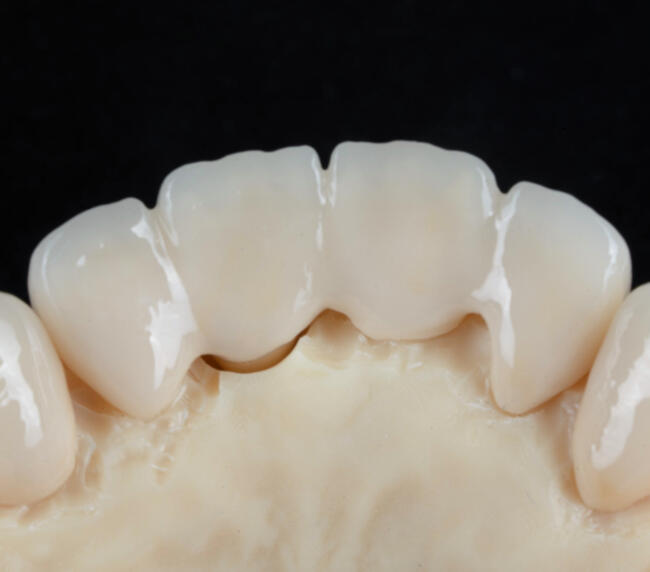

O punte dentară este o lucrare protetică fixă formată din una sau mai multe coroane dentare unite, menite să înlocuiască unul sau mai mulți dinți lipsă. Aceasta se sprijină pe dinții naturali învecinați (șlefuiți și acoperiți cu coroane) sau pe implanturi dentare în funcție de caz.

- Zirconiu – estetică premium, rezistență ridicată, biocompatibilitate 100%

- Ceramică presată – transluciditate naturală, ideală pentru zona frontală